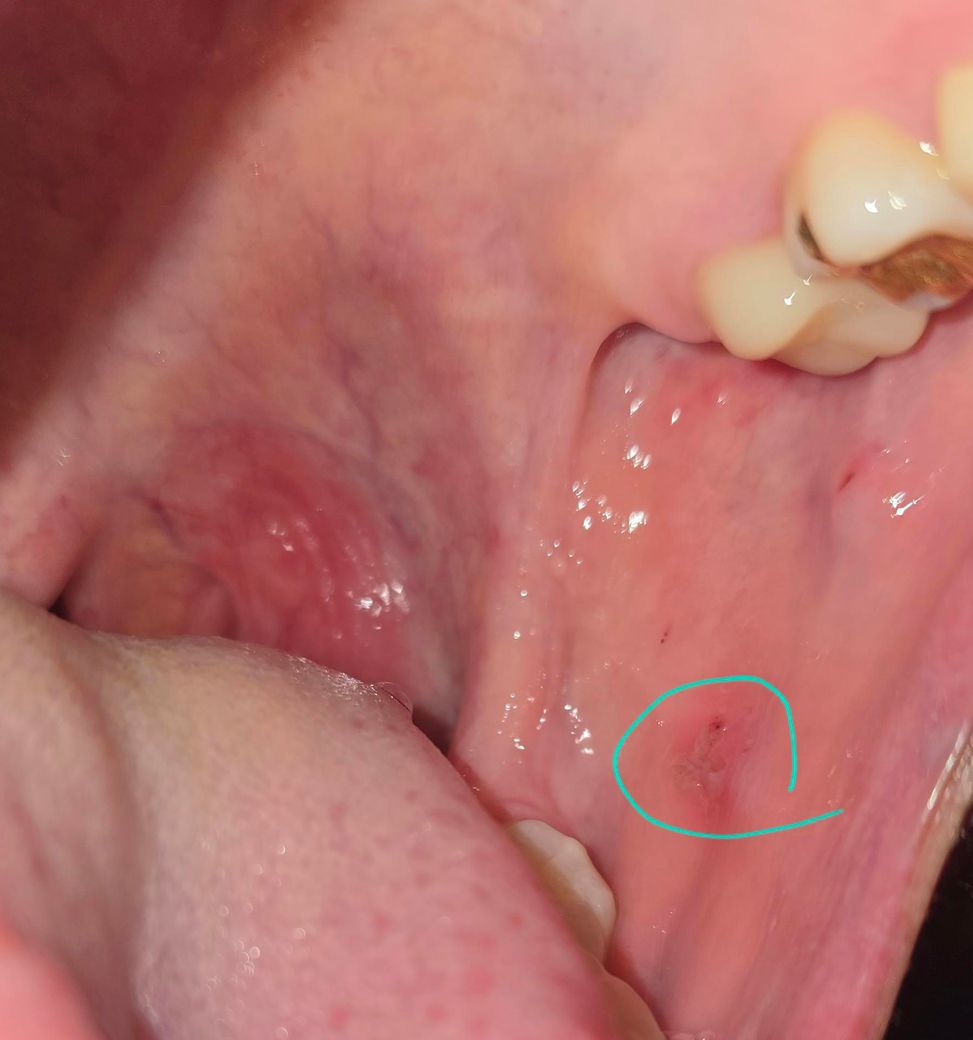

구강홍반증 일까요? 답변부탁드립니다

볼을 씹은적도없고

볼안쪽이 당기고 느낌이 혀에서 느껴지는 느낌이 매끈하지않아서

거울을보니 저상태입니다..

홍반증인지 봐주세요

사진으로 보이는 부분은 점막에 손상이 된 것으로 보입니다. 점막이 손상되고 해당 부위가 감염이 되면 구내염이 생기면서 사진처럼 보일 수 있습니다.

점막에 자극이 가해지지 않도록 하고 충분한 휴식을 취한다면 대부분 일주일 정도 지나면 없어지게 됩니다. 일주일 이상 없어지지 않는다면 자세한 확인을 위해서 치과에서 진료를 받아보는 것을 권유드립니다.